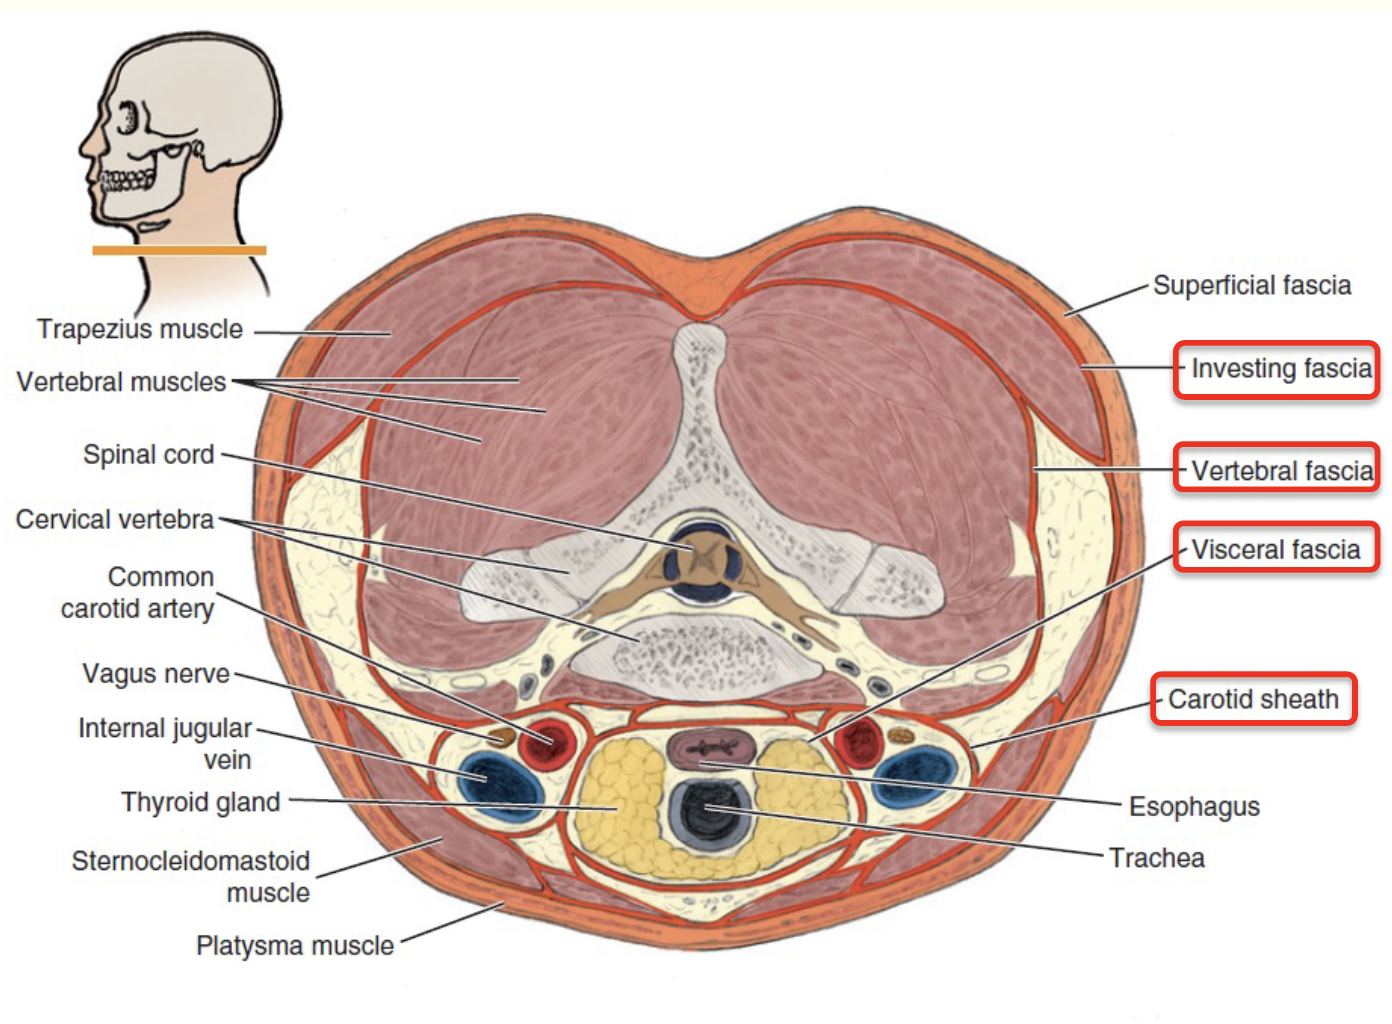

Fasciae

Superficial fascia

- 表情肌

Deep fascia

Neck

-

Investing fascia

- 最外層

-

Carotid fascia

-

Visceral fascia

- 食道呼吸道

-

Vertebral facial